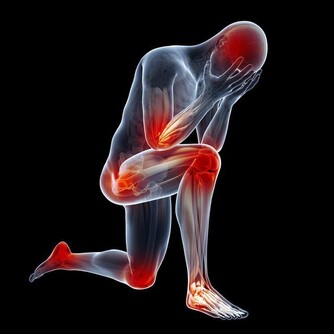

我國比較常見的慢性病有,高血壓、高脂血症、糖尿病、高尿酸血症、冠心病等,如果能夠做到將血壓、血脂、血糖、血尿酸、體重、腰圍等控制在正常範圍,可以在一定程度上減少這些疾病的發病概率。

在平時的生活中,中年人要有著規律的生活,例如三餐規律、營養均衡、勞逸結合、不要熬夜、進行運動等。對於中年人來說,他們處於一個上有老、下有小的階段,而且工作中往往也成為了領導或中堅力量。那麼良好的心態、放鬆的心情也就顯得格外重要,平時沒事爬爬山、旅個遊都是不錯的放鬆方式。